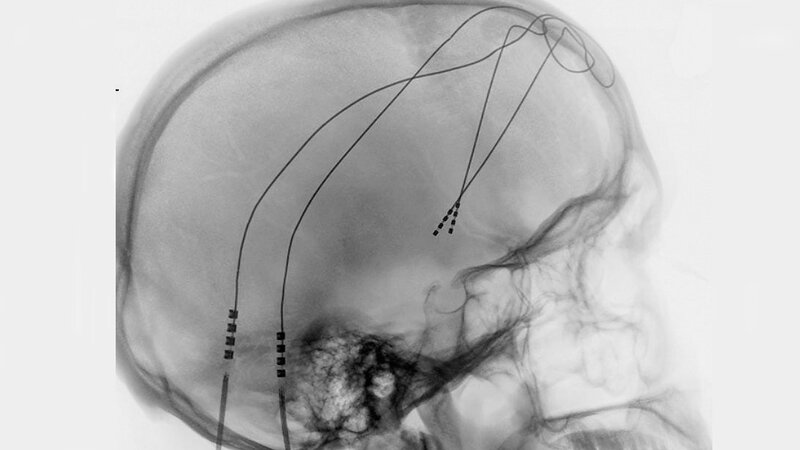

Seit etwa zehn Jahren wird versucht, diesen depressiven Patienten mit dem Therapieverfahren der tiefen Hirnstimulation zu helfen, die schon seit etwa 20 Jahren mit Erfolg auch in der Neurologie eingesetzt wird. Dazu werden in einer sogenannten stereotaktischen Operation mit Hilfe von bildgebenden Verfahren in unterschiedliche Zielregionen im Gehirn Elektroden eingesetzt. Diese werden mittels unter der Haut verlegter Kabel mit einem Generator verbunden, der ähnlich einem Herzschrittmacher die elektrische Stimulation ermöglicht. Die Wirkung dieser Therapie in verschiedenen Zielgebieten wurde systematisch untersucht und etwa der Hälfte der operierten Patienten wurde damit signifikant geholfen.

Erst kürzlich hatte der Mediziner mit einem neuen Konzept eine wichtige Verbesserung seiner Therapie erzielt. Das Forscherteam fand heraus, dass alle für die tiefe Hirnstimulation relevanten Punkte nahe beieinander liegen, nämlich im medialen Vorderhirnbündel, einem Nervenstrang, der verschiedene Punkte des Belohnungssystems miteinander verbindet. Vier Studien belegten laut Prof. Schläpfer, dass eine Stimulation von verschiedenen Teilen des Belohnungssystems starke und anhaltende antidepressive Effekte hat.

Alle Studien belegten bei ca. 85% der Probanden eine antidepressive Wirkung. Prof. Schläpfer: "Gefühle der Hoffnungslosigkeit und Antriebslosigkeit verringerten sich teilweise innerhalb von wenigen Tagen." Dieses Verfahren, glaubt der Mediziner, könnte durch die wachsende Erfahrung, die weitere technische Entwicklung der Elektroden und der Bildgebung ein viel versprechendes Mittel in der Bekämpfung der Depression sein und vielen Betroffenen Hoffnung machen. Weitere Studien müssten nun diese ersten Resultate bestätigen und zeigen, wie nachhaltig die Behandlung wirkt. Wichtig sei dabei die Interdisziplinarität des Behandlungsteams: Psychiater, Psychologen und Neurochirurgen müssten eng zusammenarbeiten. (ots, red)